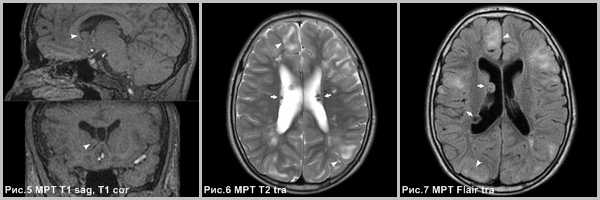

(а) МРТ, FLAIR, аксиальный срез: у трехлетнего ребенка определяется крупное супраселлярное объемное образование в форме буквы «Н», прорастающее базальные ганглии и медиальные части височных долей. Опухоль достаточно хорошо визуализируется, несмотря на размеры. Признаки перифокального отека отсутствуют.

(б) МРТ, постконтрастное Т1-ВИ, аксиальный срез: у того же пациента отмечается интенсивное однородное контрастное усиление опухоли.

(а) MPT, Т2-ВИ, аксиальный срез: у 20-месячного ребенка в супраселлярной области и медиальной части височной доли определяется крупное, массивное объемное образование. Очаги с укорочением Т2 в структуре образования могут отражать кровоизлияния (Т2* изображения получены не были).

(б) МРТ, постконтрастное Т1-ВИ, аксиальный срез: у того же пациента определяется смешанный (солидный и краевой) характер контрастного усиления. При биопсии были обнаружены удлиненные «пилоидные» клетки в матриксе, богатом муцином, что характерно для пиломиксоидной астроцитомы (ПмA).

Рис.5,6,7. Субэпендимарная гигантоклеточная астроцитома у межжелудочкового отверстия Монро в правом боковом желудочке (головка стрелки рис.5). Субкортикальные очаги гипомиелинизации (головки стрелок рис.5-7) и субэпендимарные узлы (стрелки на рис.6-7).

Субэпендимарная астроцитома возникает из субэпендимарного узла, рядом с отверстием Монро, отличается от других узлов тем, что накапливает контраст, имеет больший размер и растет. Таким образом, пациентам с подтвержденным диагнозом болезни Бурневилля-Прингла необходимо проводить МРТ с контрастом по меньшей мере 1 раз в год, по крайней мере, до 20 лет. Субкортикальные очаги повышенной интенсивности МР-сигнала по Т2 и Flair являются участками гипомиелинизации и глиоза [79]. Субэпендимарные узлы состоят из глиальных клеток и гигантских или многоядерные клеток, покрытых слоем эпендимы [137].